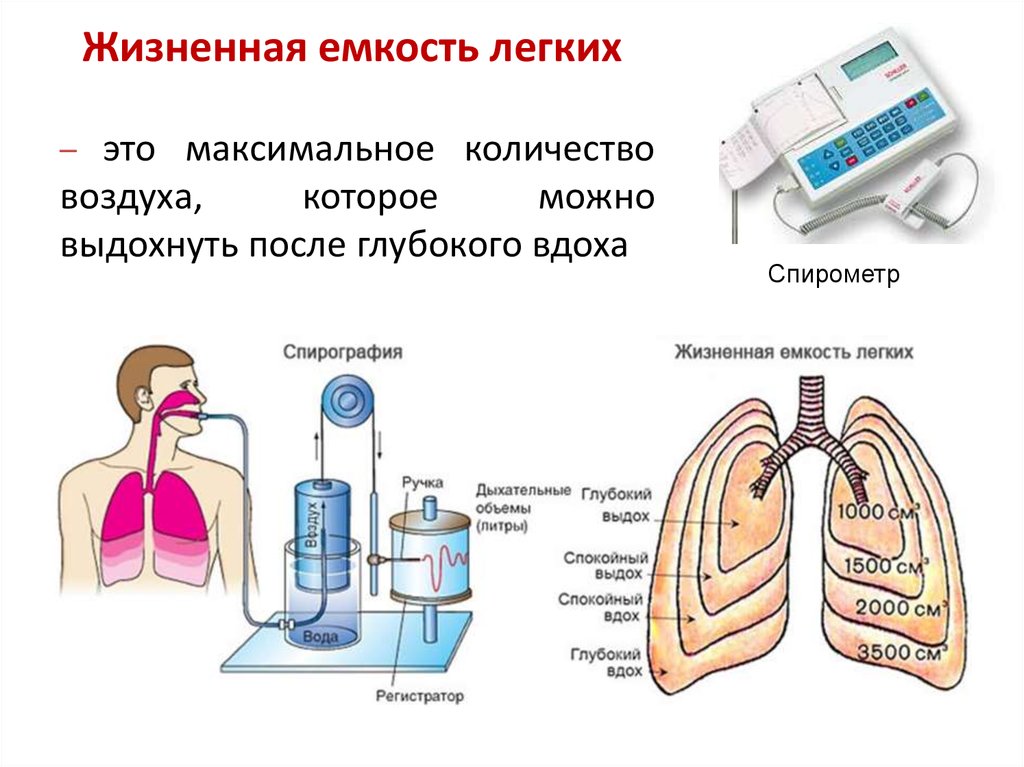

Роль легких в метаболических процессах